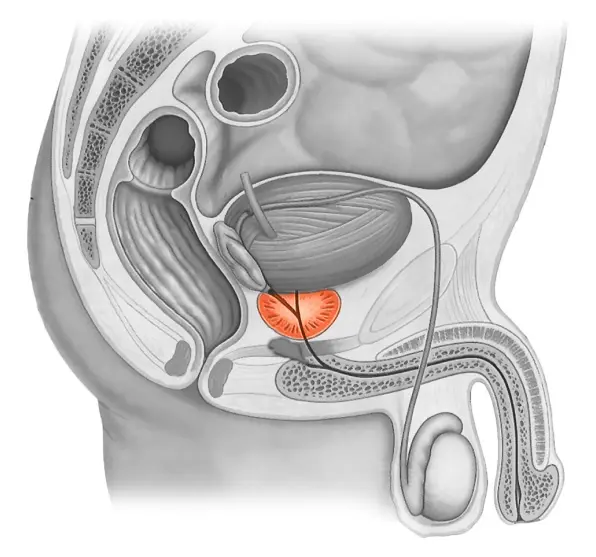

سڑا ہوا پروسٹیٹ اور اڈینوما

سب کچھ آسان ہے: پروسٹیٹ میں سیمینل سیال پیدا ہوتا ہے، اور نئے سیال کے لیے جگہ بنانے کے لیے اسے وقتاً فوقتاً چھوڑا جانا چاہیے۔ لیکن اگر آدمی نامرد ہو جائے تو اس کے اندر کی رطوبت رک جاتی ہے۔ یہ بنیادی طور پر پروٹین پر مشتمل ہوتا ہے، اور وقت کے ساتھ ساتھ یہ سڑے ہوئے انڈے کی طرح گلنا شروع ہو جاتا ہے۔

پیتھوجینک مائکروجنزم اور بیکٹیریا پروسٹیٹ میں بڑھ جاتے ہیں۔ بیکٹیریل پروسٹیٹائٹس تیار ہوتا ہے۔ غدود کے ؤتکوں میں ناقابل واپسی تبدیلیاں واقع ہوتی ہیں۔ یہ پروسٹیٹ اڈینوما کی طرف جاتا ہے - ایک سومی تشکیل (پیتھوجین کی موجودگی کی وجہ سے، خلیات ناکافی طور پر تقسیم ہونے لگتے ہیں)۔

اڈینوما کیا ہے؟ یہ بہت خطرناک حالت ہے۔ یہ اکثر اونکولوجی کی ترقی اور ایک مہلک نتیجہ کی طرف جاتا ہے.

بدقسمتی سے، پروسٹیٹ ٹشو بہت نازک ہے، اور اس وجہ سے مندرجہ بالا تمام تیزی سے تیار ہوتے ہیں. پہلی علامات سے لے کر ناقابل واپسی حالت تک، صرف چند سال گزر سکتے ہیں۔

پروسٹیٹ کی صفائی

جیسا کہ میں پہلے ہی کہہ چکا ہوں، نامردی، حتیٰ کہ قلیل مدتی، پراسٹیٹ کو شدید دھچکا دیتی ہے، جو دائمی پروسٹیٹائٹس کو بھڑکاتی ہے۔ بہت سے مرد اقدامات کرتے ہیں، لیکن عام طور پر ناکام رہتے ہیں، کیونکہ سیمینل سیال کی کوئی تجدید نہیں ہوتی ہے۔ Prolan جنسی آزادی اور پروسٹیٹ کی صفائی میں حصہ ڈالتا ہے، لہذا اس کی صحت خود بخود بحال ہوجاتی ہے۔ دائمی پروسٹیٹائٹس غائب ہوجاتا ہے۔ اگر کسی مرد کو پہلے سے ہی پروسٹیٹ اڈینوما ہے، تو Prolan تھراپی کے بعد صحت یابی میں حصہ ڈالے گا۔